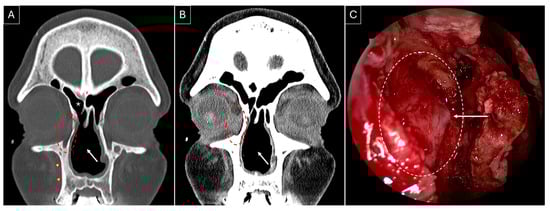

Case 1: A 48-year-old female patient presented in February 2021 with complaints of nasal congestion, drainage, facial pressure, and pain for 18 months. She had a poor response to medical management and developed loss of smell, altered taste sensation, left-sided epiphora, nasal bridge collapse, and diabetes insipidus, and underwent multiple failed endoscopic sinus surgeries. A solitary lesion in the lung was identified, and its biopsy was suggestive of GPA. She was prescribed rituximab with prednisone in December 2020. She was later diagnosed with subglottic stenosis and developed bilateral epiphora (left > right) in May 2021. She was stabilized on methotrexate, prednisone, and rituximab and tested negative for cytoplasmic anti-neutrophil cytoplasmic antibodies (cANCA). She underwent endoscopic DCR on her left side with the placement of Crawford stents in April 2022. Intraoperative findings included distorted anatomy, regression of bilateral middle turbinates, and formation of dacryocystocele (Figure 2). Stents were removed after three months. Granulation tissue formed at the site of DCR that needed repeated debridement to maintain patency of the stoma, which stabilized by the fifth postoperative month.

Figure 2.

Non-contrasted sinus CT, coronal section, showing left-sided dacryocystocele (red dotted circle) in contrast to the right-sided lacrimal sac (white dotted circle). Presence of a nasal septal perforation (white arrow) and osteitic bone remodelling (red arrowheads) can be noted in both bone (A) and soft tissue (B) windows.